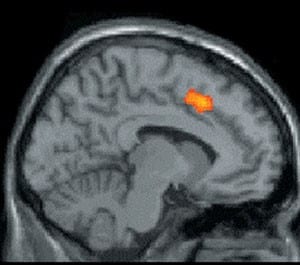

អារម្មណ៍ឈឺចាប់ទាំងឡាយ ដូចជាពេលដែលអ្នកជាមនុស្សចុងក្រោយដែលត្រូវបានគេជ្រើសរើសចូលក្រុម សុទ្ធតែបានកត់ទុកនៅក្នុងខួរក្បាល។ បើយោងទៅតាមការសិក្សាស្រាវជ្រាវថ្មីៗនេះបានរកឃើញថាខួរក្បាលឆ្លើយតបទៅនឹងការបដិសេធដូចគ្នាទៅនឹងការឈឺចាប់ផ្នែករាងកាយអ៊ីចឹងដែរ។ ការរកឃើញនេះបង្ហាញថាតម្រូវការសម្រាប់ការដាក់បញ្ចូលទិន្នន័យទៅក្នុងខួរក្បាលគឺព្យាយាមក្នុងការជៀសវាងពីការឈឺចាប់។

មនុស្សដែលធ្លាប់ត្រូវបានគេបដិសេធប្រាកដជាយល់នៃភាពឈឺចាប់នេះ។ ក្នុងការស៊ើបអង្កេតពីការបដិសេធចំពោះខួរក្បាលត្រូវបានធ្វើឡើង សមាជិកនៃអ្នកស្រាវជ្រាវក៏បានស្ម័គ្រចិត្តពាក់ម៉ាស៊ីនមុខងារអនុភាពម៉ាញេទិចនៃរូបភាព និងការតាមដានសកម្មភាពខួរក្បាល។ អ្នកស្ម័គ្រចិត្តបានពាក់វ៉ែនតាពិសោធន៍ដែលអនុញ្ញាតឲ្យពួកគេលេងហ្គេម Cyberball ដែលជាហ្គេមមួយដែលមានអ្នកលេង ៣នាក់បោះបាល់ទៅវិញទៅមក។

អ្នកលេង២នាក់ជាអ្នកលេងដែលគ្រប់គ្រងដោយកុំព្យូទ័រ ហើយបន្ទាប់ពីលេងបានមួយសន្ទុះអ្នកស្ម័គ្រចិត្តនោះត្រូវបានអ្នកលេងពីរនាក់ផ្សេងដែលគ្រប់គ្រងដោយកុំព្យូទ័រមិនអើពើ មិនបោះបាល់ឲ្យលេង។ បន្ទាប់ពីលេងចប់អ្នកស្ម័គ្រចិត្តនោះត្រូវបានអ្នកស្រាវជ្រាវសម្ភាស ដោយពួកគេនិយាយថាតើអ្នកបានឃើញអ្វីដែលពួកគេបានធ្វើចំពោះខ្ញុំទេ ខណៈខ្លះទៀតសង្ស័យថាអ្នកស្រាវជ្រាវចង់ធ្វើអ្វីទៅលើពួកគេ។

ពេលដែលអ្នកស្ម័គ្រចិត្តលេងហ្គេមចប់ ផ្នែកមួយនៃខួរក្បាលហៅថា anterior cingulate cortex (ACC) ដែលឆ្លើយតបទៅនឹងការឈឺចាប់ដែលកើតឡើងនោះពិតមែន យោងទៅតាមការរបាយការណ៍នៃការឆ្លើយតបរបស់អ្នកលេងហ្គេមនោះចំពោះការបដិសេធ។ អ្នកស្រាវជ្រាវក៏បានរកឃើញភាពសង្ស័យមួយចំនួនផ្សេងទៀត ដោយផ្នែកខ្លះទៀតនៃខួរក្បាលព្យាយាមទប់ស្កាត់ និងដោះស្រាយបញ្ហាដែលបានកើតឡើង(ការឈឺចាប់ពីការបដិសេធ) ដោយវាចាប់ផ្ដើមបញ្ចេញសញ្ញាពីផ្អែកមួយនៃខួរក្បាលដែលហៅថា ACC នោះ៕